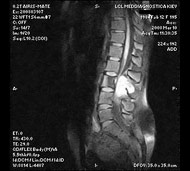

Спинальна магнітно-резонансна томографія (МРТ). Замість радіаційного випромінювання в МРТ використовуються потужні магнітні і радіохвилі для отримання зображення поперечного перерізу хребта. МРТ чітко відображає спинний мозок і нерви і забезпечує краще зображення пухлин кісток, ніж комп'ютерна томографія (КТ). Вам можуть ввести в вену кисті або передпліччя контрастну речовину, яка висвітлює деякі пухлини. Крім цього, використовують сканери з високою інтенсивністю сигналу для виявлення невеликих пухлин, які можна не помітити.